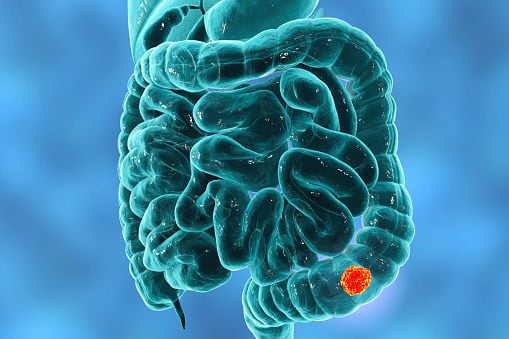

“There is a precursor lesion of colon cancer called an 'adenomatous polyp', or adenoma, which, if detected and removed by colonoscopy, can prevent the disease. This implies that thanks to this study we can avoid colon and rectal cancer, with the emotional and physical health benefit that this implies: we avoid going through diagnosis and treatment. For those cases in which the already malignant polyp (cancer) is detected, early detection can prevent more invasive treatments with cure rates of around 90%, whereas if it is detected late; although the scenario is much more complex, fortunately today we have therapeutic alternatives that allow to improve the quality of life and prognosis of the disease”, explained Dr. Karina Collia, Proctologist Surgeon and Member of the Coloproctology Service of the Gastroenterology Hospital 'Dr. Carlos B. Udaondo.